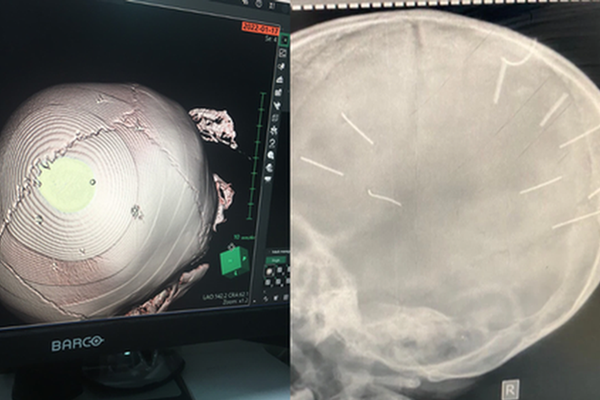

Trước đó, chiều tối 17/1, Bệnh viện Đa khoa huyện Thạch Thất tiếp nhận bé gái Đ.N.A., 3 tuổi, xã Canh Nậu, nhập viện trong tình trạng hôn mê và co giật. Bé A. được chuyển lên Bệnh viện Đa khoa Xanh Pôn, sau khi chụp chiếu phát hiện 9 vật thể nghi là đinh trong sọ não.